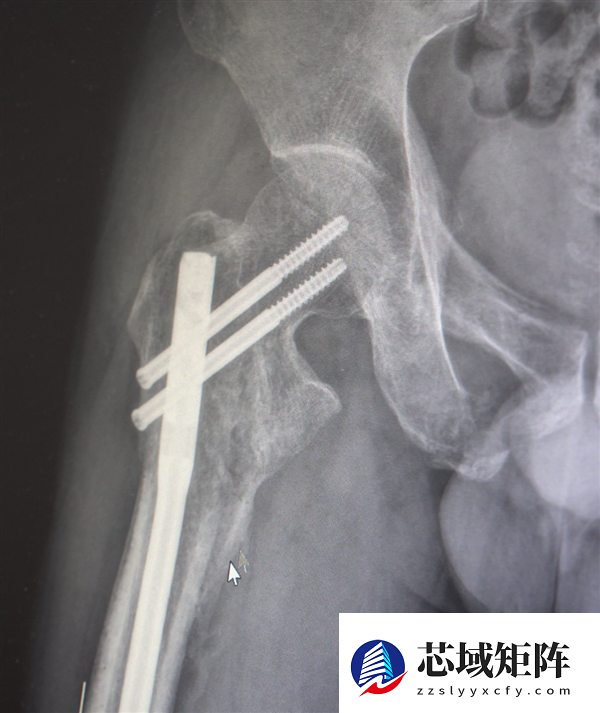

创伤性失血性休克、多发性肋骨骨折、肺部损伤、右侧肩胛骨粉碎骨折、右侧肱骨髁上开放粉碎性骨折、右股骨粗隆及股骨干粉碎性骨折、骨盆粉碎性骨折、腰椎横突多发骨折、腰骶柱神经损伤、臂丛神经损伤、胸腔积液、腹腔积液等。

经医生检查,张先生全身共有六处较大骨折部位,多为严重粉碎性骨折,全身骨折碎块达30多块!

部分手术后拍摄的影像